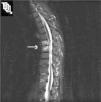

Ante estos hallazgos se diagnosticó de espondilodiscitis aséptica a nivel de D7-D8 y L1-L2, junto con aplastamiento vertebral de D12 de origen osteoporótico. Se inició tratamiento anti-TNF en julio de 2004, con etanercept a dosis de 25mg 2 veces a la semana, ante la falta de respuesta a antiinflamatorios no esteroideos (AINE) y sulfasalazina. Se realizó conjuntamente quimioprofilaxis con isoniazida durante 9 meses ante el resultado positivo del PPD y tratamiento con calcio y vitamina D por los hallazgos densitométricos. A las 4 semanas de inicio del tratamiento, la paciente mejoró clínicamente con desaparición del dolor dorsolumbar y normalización de los reactantes de fase aguda. En la exploración presentaba un test de Schober modificado de 1,5cm, distancia dedos-suelo de 0cm, BASFI de 11 y BASDAI de 0. En enero de 2005 se realizó una RM de columna dorsal STIR de control (fig. 2) en la que no había signos de actividad inflamatoria osteodiscal a nivel de D7-D8. Al año de tratamiento se observó también una mejoría en los valores de la densitometría ósea (lumbar: T-score, -1,35, y femoral: T-score, -0,02) con respecto a la previa. La paciente continúa actualmente asintomática con la terapia anti-TNFα.

Resonancia magnética de columna dorsal de control, corte sagital con secuencia STIR: se observa una resolución completa de la espondilodiscitis a nivel de D7-D8, con sustitución grasa y sin signos indicativos de actividad inflamatoria osteodiscal. El resto, sin cambios respecto a la previa.